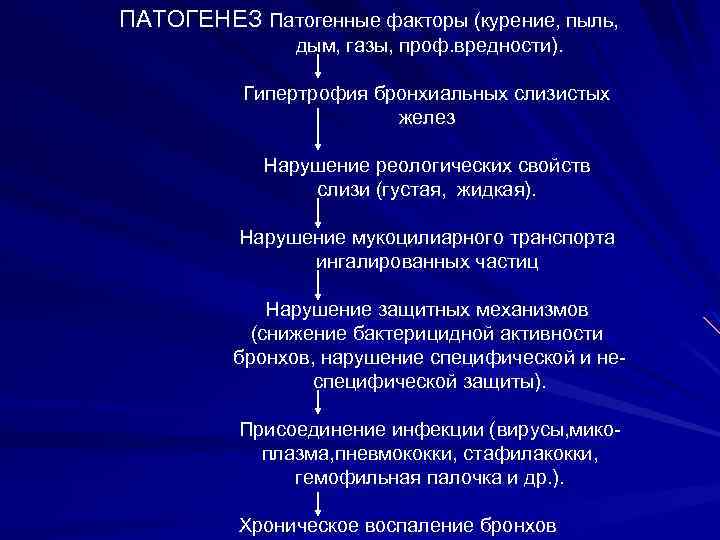

ПАТОГЕНЕЗ Патогенные факторы (курение, пыль, дым, газы, проф. вредности). Гипертрофия бронхиальных слизистых желез Нарушение реологических свойств слизи (густая, жидкая). Нарушение мукоцилиарного транспорта ингалированных частиц Нарушение защитных механизмов (снижение бактерицидной активности бронхов, нарушение специфической и неспецифической защиты). Присоединение инфекции (вирусы, микоплазма, пневмококки, стафилакокки, гемофильная палочка и др. ). Хроническое воспаление бронхов